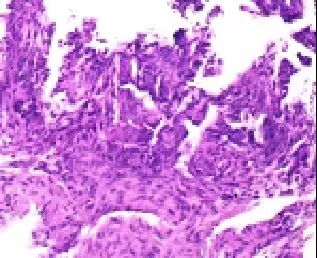

患者术中及术后无其他不适,安返病房。样本经病理科固定、切片、染色与显微镜观察,最终,确诊患者为胰腺癌,为其进一步确定治疗方案提供了充分的依据。此次穿刺活检术是赤峰市医院CT室微创介入团队完成的一例高难度胰腺占位性病变穿刺活检术,填补了赤峰市该项技术的空白,标志着赤峰市胰腺诊疗技术越来越规范,越来越精准。